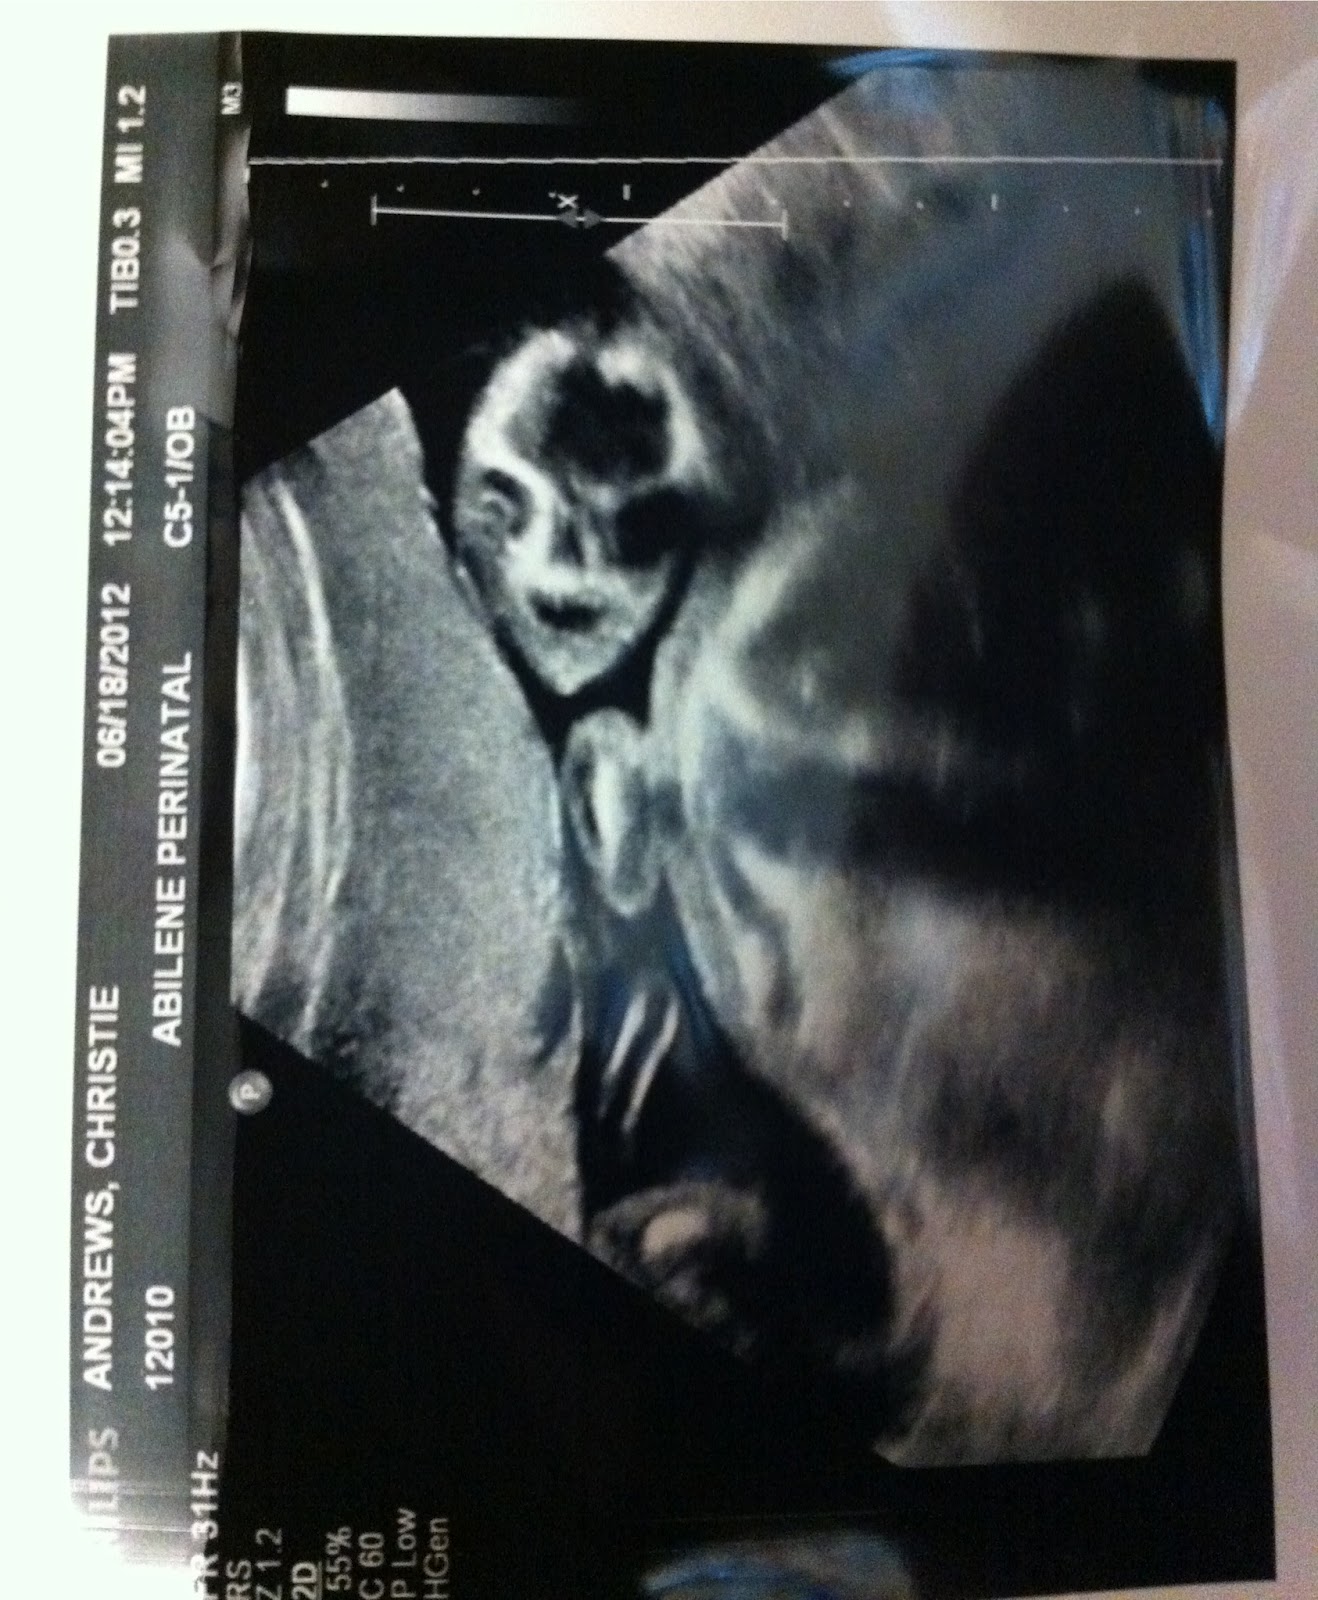

And in the name of pure celebratory feeling, I will share with you our little Gummi's picture from the day we found out he was a boy.  A picture that might be the most terrifying thing to ever make me laugh.